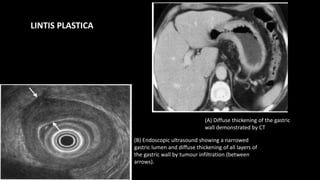

(B) Endoscopic ultrasound showing a narrowed

gastric lumen and diffuse thickening of all layers of

the gastric wall by tumour infiltration (between

arrows).

(A) Diffuse thickening of the gastric

wall demonstrated by CT

LINTIS PLASTICA